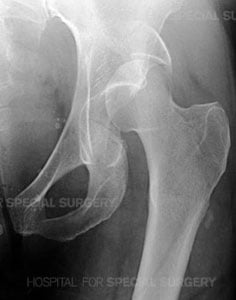

Radiograph of the left hip demonstrating a posterior dislocation of the hip with an associated

Posterior Wall type fracture of the acetabulum